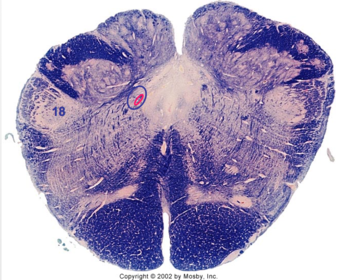

| Nucleus gracilis | |

| Accessory nucleus | |

| Medial longitudinal faciculus | |

| Pyramidal decussation | |

| Medullary pyramids | |

| Anterior spinocerebellar tract | |

| ALS | |

| Posterior spinocerebellar tract | |

| Spinal tract of V | |

| Spinal nucleus of V | |

| Nucleus cuneatus | |

| Fasciculus cuneatus | |

| Fasciculus gracilis | |

| Central canal | |